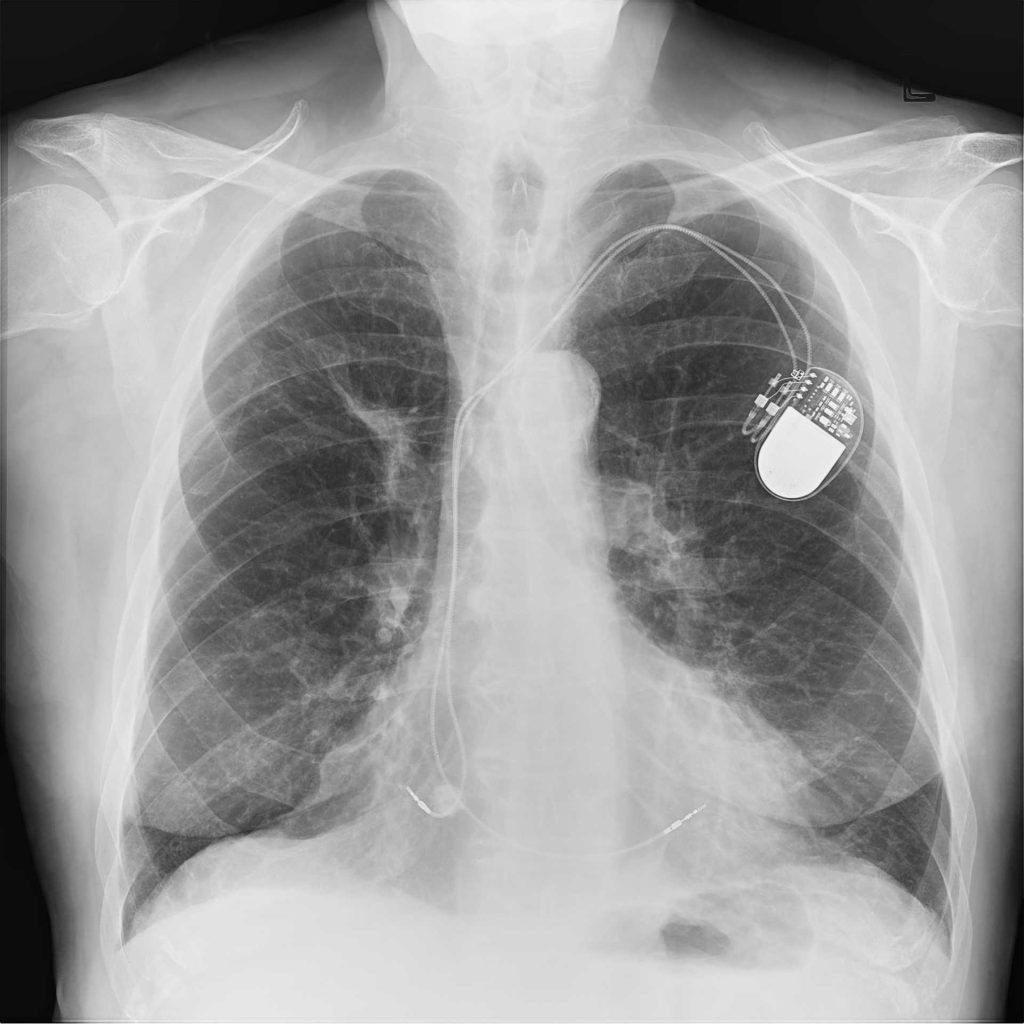

Reveal 35C has a triple layer design which simultaneously captures three images in a single exposure, all without motion artifacts. To do this, the Reveal 35C only requires the standard radiation dose. The dosage does not need to be increased to achieve dual-energy imaging.

Of the three images is a traditional DR image which captures both bone and soft tissue, as well as supplemental bone and soft tissue images. This enables easy material differentiation for radiologists.

On the left is the traditional DR image, in the middle is the soft tissue image, and on the right is the bone image.